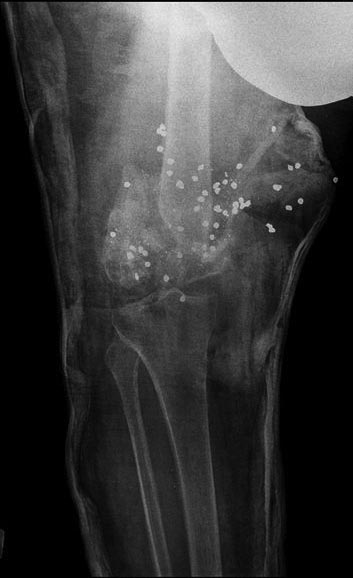

в 2009 году я получила несколько огнестрельных ранений(дробь) и одно ранение в ногу в область коленного сустава и одно ранение в ногу в область коленного сустава и вот на протяжении уже более 4 лет мне не могут помочь срастить перелом перенесла 4 операции по налажению аппарата Илизарова две операции в августе 2009 года и находилась в нем по апрель 2010 года, нога не срослась...местные республиканские врачи( проживаю в Республики Хакасии) сказали,что ни чем не могут помочь, только в 2011 году меня согласились прооперировать в клинике Илизарова в г.Кургане в 2012 году с марта месяца и по 2013 год август я находилась в аппарате илизарова за этот период, было сделано три операции, но результатов положительных это не дало в августе меня выписали с клиники сняли аппарат наложили лангету и выписали с диагнозом имеются ренгенологические признаки консолидации отломков дистального отдела правой бедренной кости,щель коленного сустава дисконгруэнтна так же имеются множественное количество инородных тел дробь..после посещения уже наших врачей они сказали что перелом не срастется совсем и сейчас я нахожусь в лангете, нога все чувствует нет свищей и нет нагноений мышцы не ослаблены я постоянно занимаюсь изометрическими упражнениями...На данный момент были сделаны снимки новые и диагноз несрастающийся перелом ,Помогите нет сил терпеть боль столько лет..прилагаю снимки ..

Ситуация здесь непростая. Стандартное эндопротезирование тут не годится, нужен ревизионный или онкологический протез, да и риск инфекции очень высок. Эндопротезирование коленного сустава делают и в Курганском РНЦ, где Вы уже были. Обсуждали там этот вариант?

Можно обсуждать артродез (замыкание) коленного сустава с остесинтезом длинным внутрикостным стержнем бедро-голень. Сравнительных снмков нет, еще и про укорочение то есть нет информации.